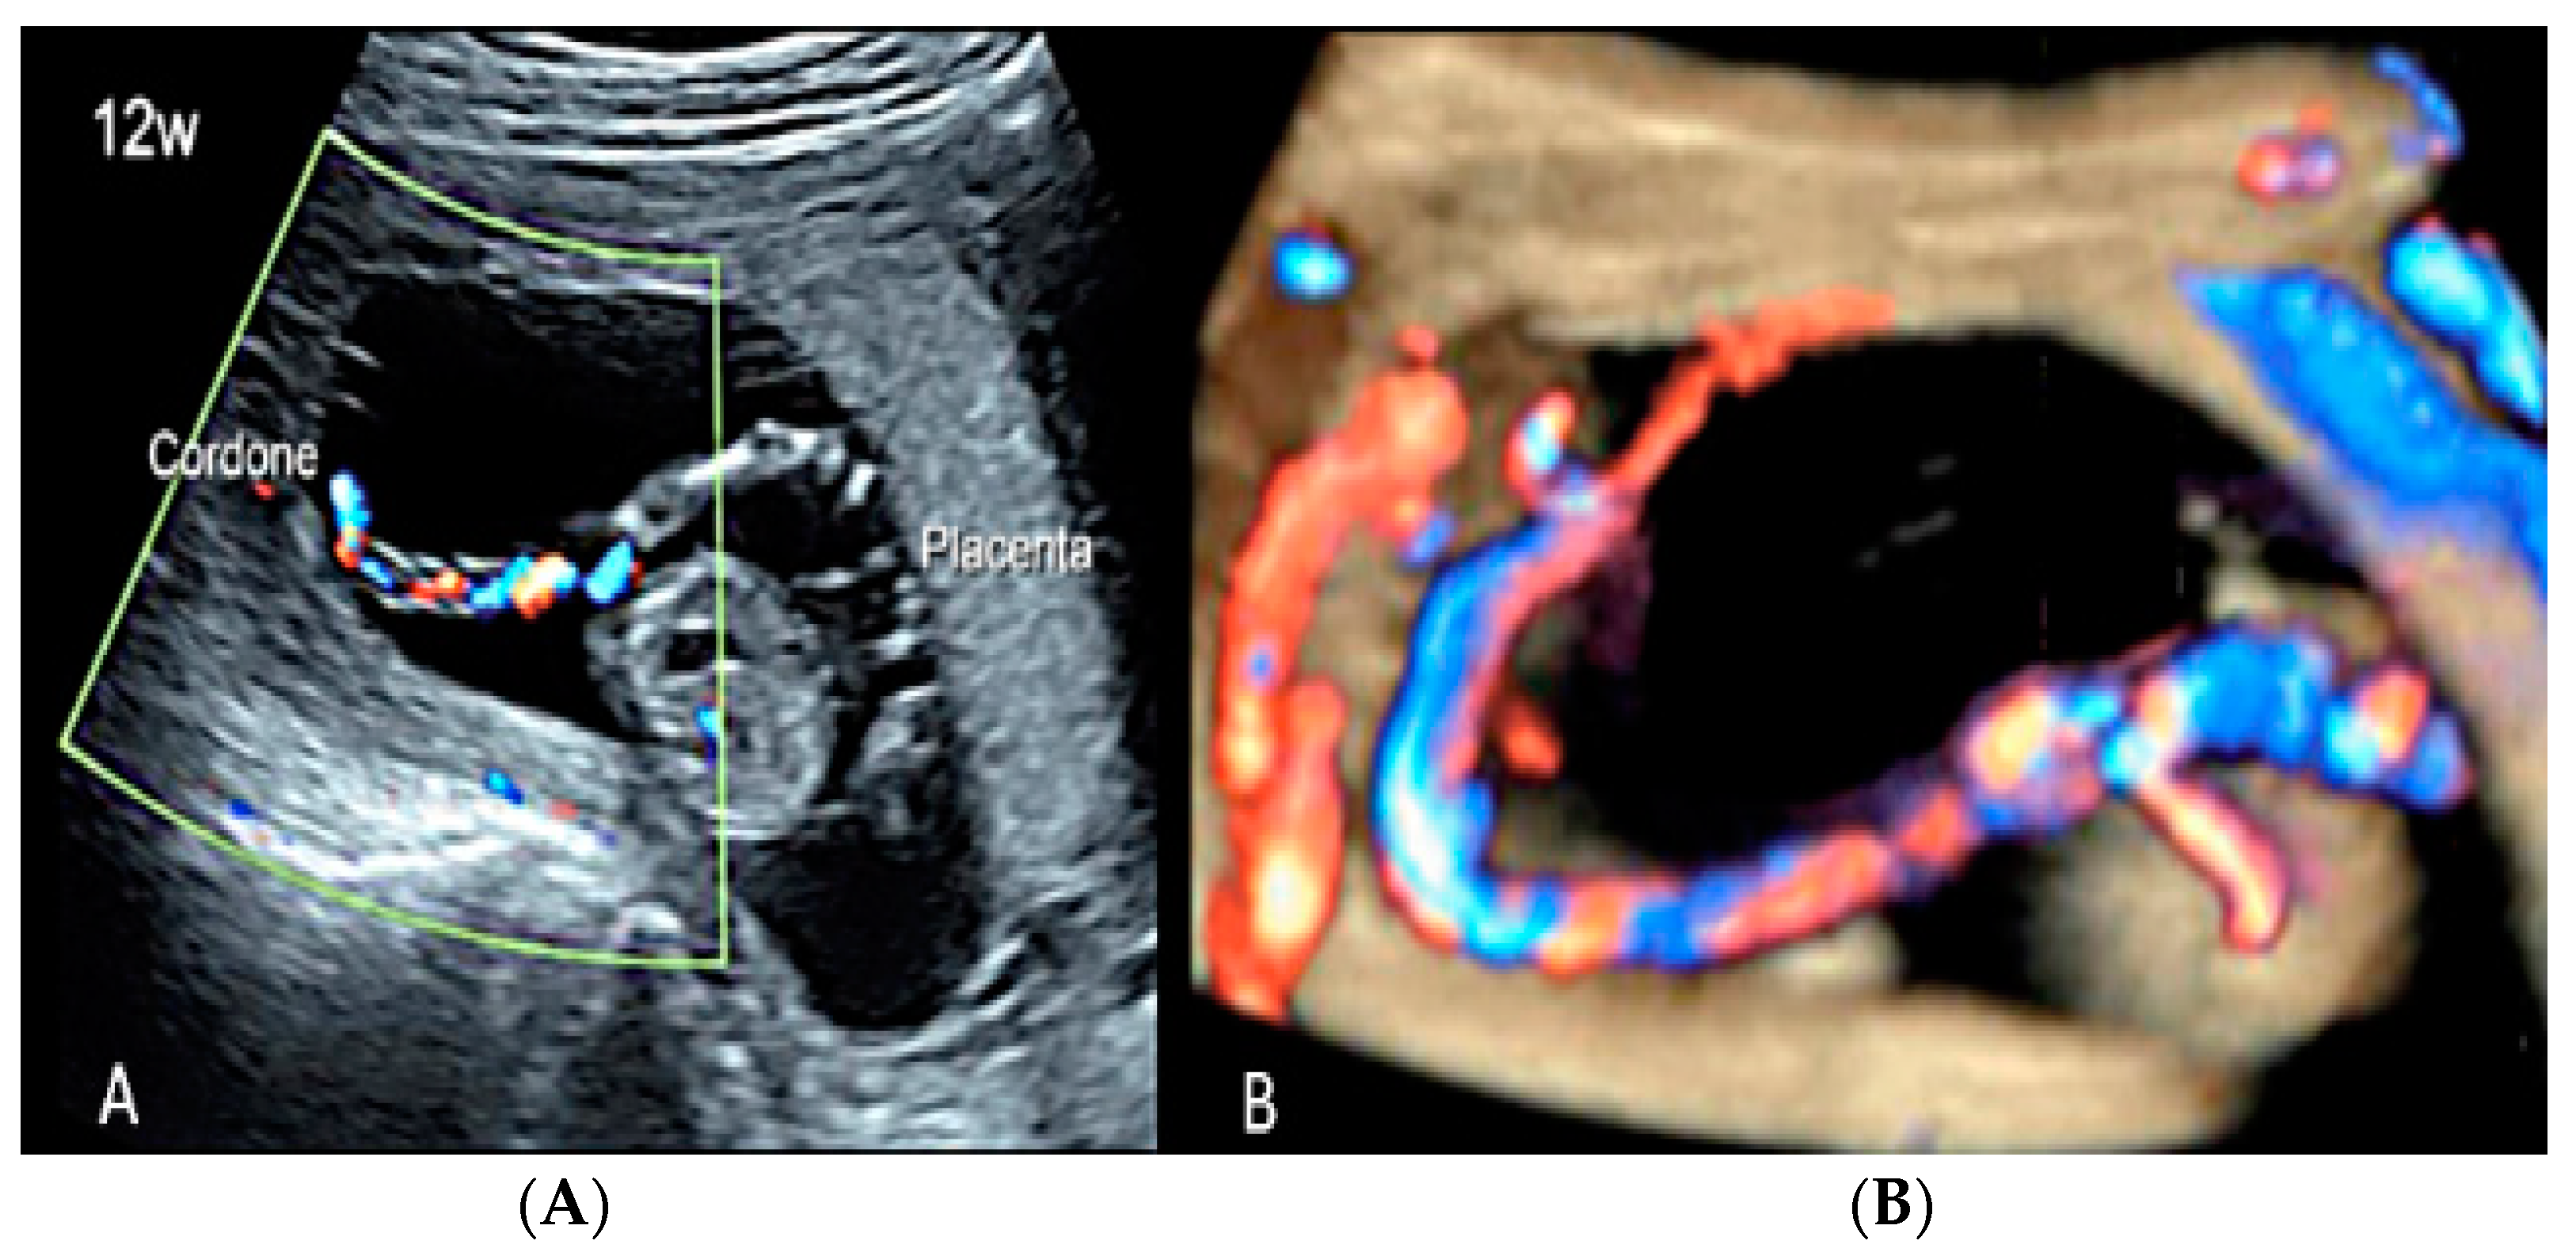

3.2.3. Velamentous Umbilical Cord Insertion

3.2.4. Marginal Umbilical Cord Insertion